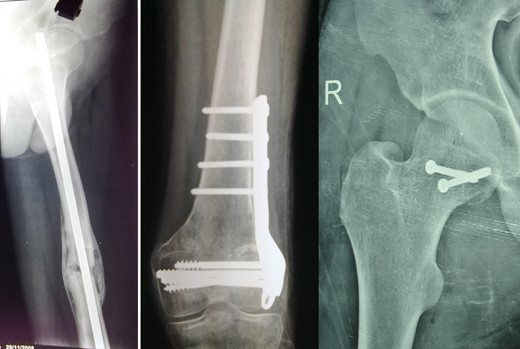

The right hip joint was approached via the Kocher-Langenbeck approach, fracture site was exposed with removal of fibrous tissue and the fracture involved mostly the infrafoveal non-weight bearing surface of the femoral head (Fig. 4). Following reduction of fracture, femoral head was fixed with two 4 mm cannulated cancellous screws that were introduced over a guide wire from the non-articular part under C-arm guidance (Fig. 5). Open reduction and plating was performed for the ipsilateral femoral condylar fracture. Closed reduction and intramedullary nailing of left femur was performed in the same sitting. The immediate postoperative X-ray was satisfactory (Fig. 6). The postoperative period was uneventful.

At 1- and 7-year follow-up, X-rays were satisfactory with no signs of osteonecrosis of femoral head (Figs 7 and 8). Nail from the left femur and right distal femoral plate were removed at the end of 2 years. The patient at 7 years post-surgery had a good functional assessment (Friedman and Wyman) score with X-ray bearing no signs of avascular necrosis or heterotrophic ossification, and the fracture had united. Over 7 years, patient who is a student by profession is bearing full weight and is successfully performing his personal and social duties. The active range of motion at right hip was 0–110° flexion and 0–10° extension, external rotation 0–30° with internal rotation 0–10° with slight loss of terminal abduction (Figs 9 and 10).